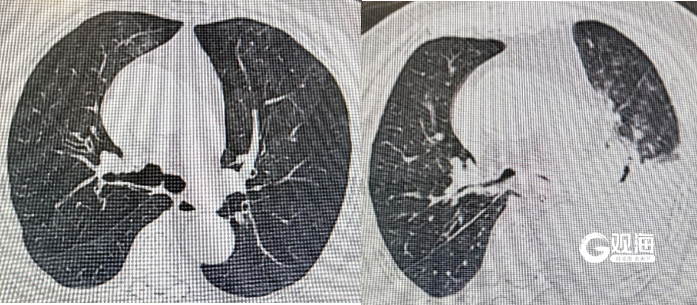

据悉,老人到达急诊时,血氧饱和度极低,呼吸困难进行性加重,已处于呼吸衰竭状态。 胸部CT显示两肺弥漫性渗出,吸入性肺炎诊断明确。更棘手的是,污水中的多种病原体迅速引发严重感染,并出现了急性呼吸窘迫综合征(ARDS),这种溺水后最危险的并发症之一,病死率极高,医院立即启动多学科联合救治机制。救治团队制定了一套分层推进、多管齐下的精准救治方案。

88岁高龄患者器官储备功能差,救治过程中任何一次感染加重、循环波动或药物不良反应都可能引发连锁反应。呼吸与危重症医学科与影像科、检验科、临床药学等多学科团队建立每日联合查房制度,动态评估肺部影像变化、感染指标及脏器功能,及时调整治疗策略,确保每一个关键决策都精准稳妥。